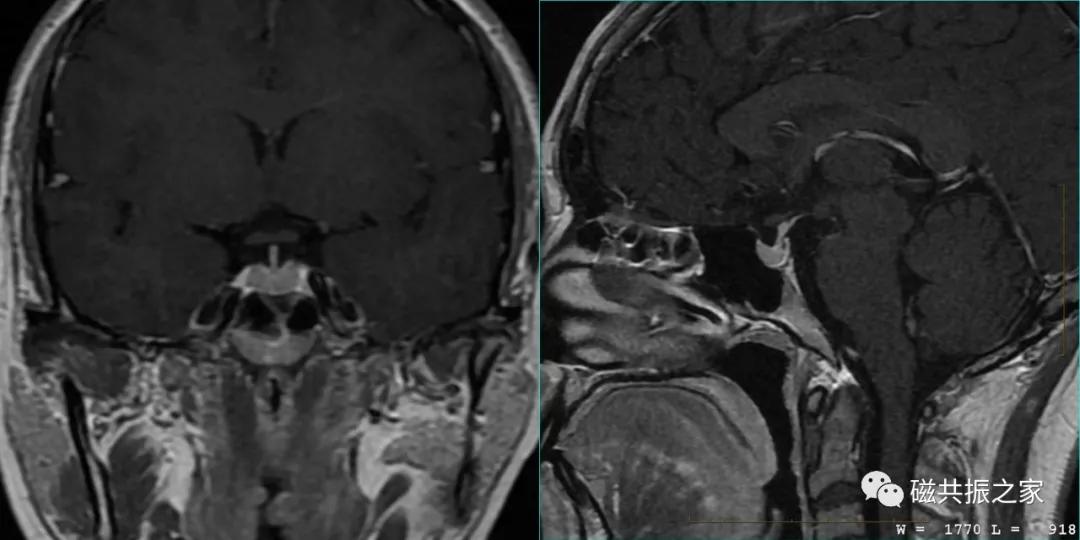

最理想的冠状位图像:同一层面视交叉、垂体柄和垂体均能清晰显示,共同组成“工”字结构。

冠状位是观察垂体柄形态和测量垂体高度最理想的方位。

矢状位是显示垂体前后叶最理想的方位。

以矢状位和横断位作为参考定位。在矢状位上定位线垂直于鞍底(或平行于垂体柄或垂直于垂体窝),在横断位上与大脑纵裂垂直,双侧对称扫描,扫描范围包括整个垂体,根据病变大小调整范围,需包括整个病变范围。